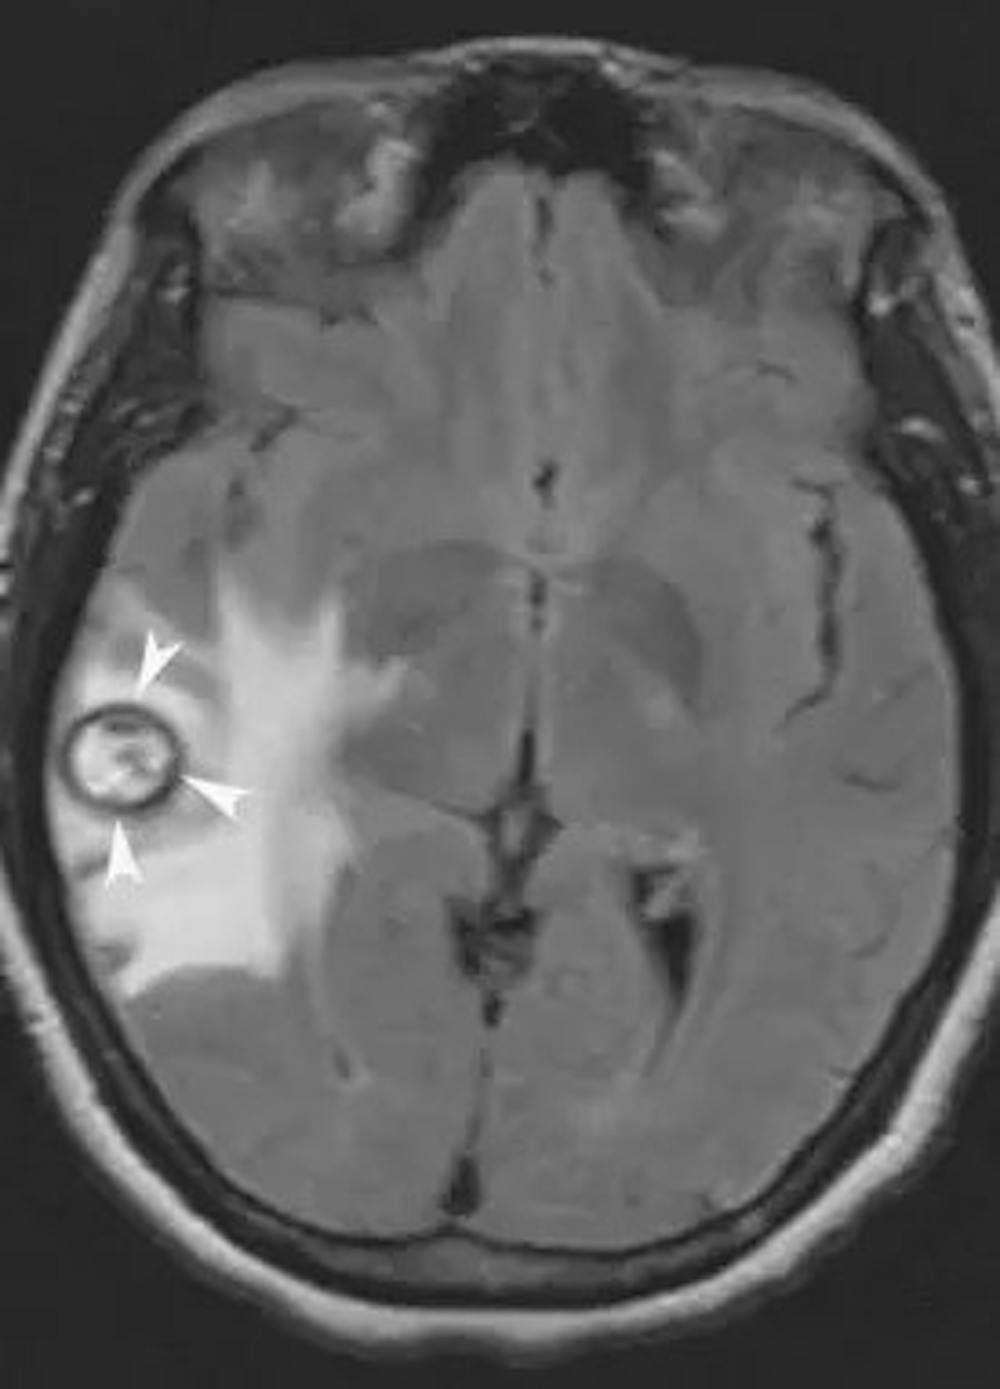

海綿狀血管瘤患者可能表現為新發癲癇發作、進行性神經功能缺損和偶爾的腦出血。 海綿狀血管瘤往往有反覆的小出血,很少對神經造成破壞性。 海綿體瘤出血的年風險範圍為0.2%至2%。 洞穴瘤通常在 MRI 上診斷,因為它們具有非常典型的外觀。

顯示右顳海綿體瘤的大腦軸向序列。 注意海綿狀體周圍的黑環(箭頭)。 這個環稱為含鐵血黃素環,起源於小出血事件后沉積在海綿狀血管瘤周邊的舊血液製品。 這種含鐵血黃素環是海綿體瘤的特徵。